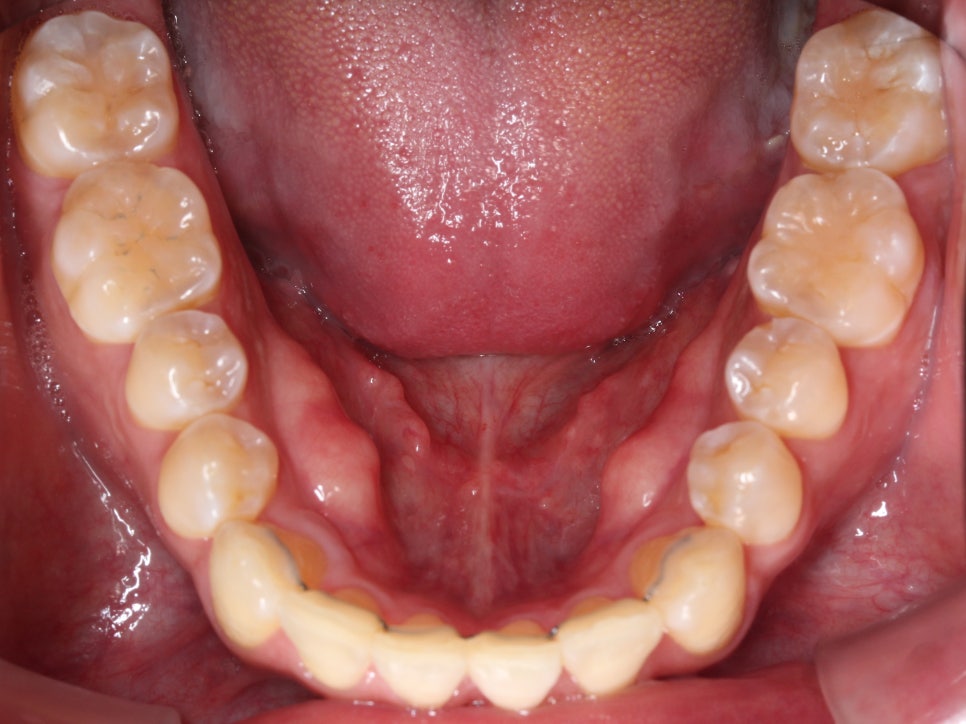

아래 앞니도 공간이 부족해서

약간 삐뚤빼뚤한 모습이 나타나지만

충분히 비발치 부분교정으로

펼칠 수 있는 케이스라 판단했습니다.

아래 치아는 배열될 공간을 만들기 위해

치간 삭제를 동반하여 치료하고 있었고

치간 삭제를 하면서 아래 치아 각도가

조금 더 개선이 되었습니다.